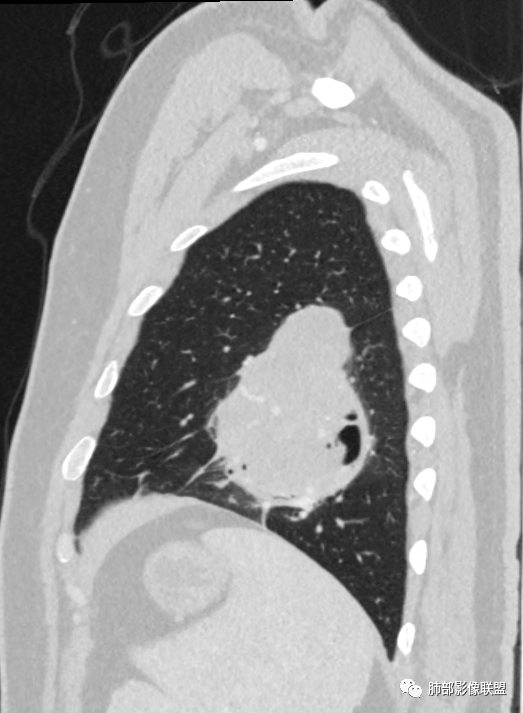

骑跨在斜裂上

局部斜裂稍增厚

空气新月征:

新月征很有特点,血管有特点

定位比较明确,定位胸膜就不考虑曲菌球

边缘光滑

蛇纹血管像sft,空气新月征像psp

叶间裂没有推移,好像是sft这种内部气体影是一个特点。

青年男性,体检发现左肺不规则类圆形占位性病变,叶间裂区域,定位胸膜来源。左肺下叶支气管受压狭窄,但管壁光整,未见腔内阻塞或管壁受侵。包块边界清晰,浅分叶,内部密度不均匀,病灶后份见空气新月征。渐进性强化,增强动脉期见分支状血管,蛇纹血管征。肺门纵膈未见增大淋巴结,符合孤立性纤维瘤(SFT)。